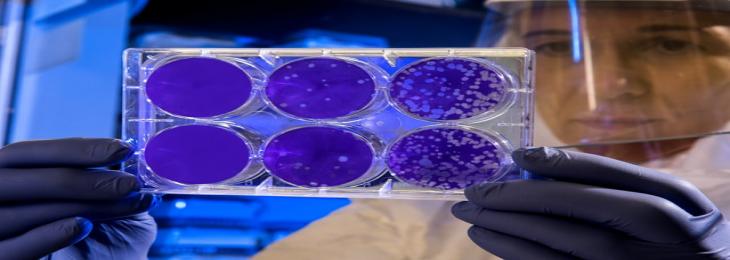

A new study found that specific type of gut bacteria hoard consumed drugs restricting their efficiency. There are numerous bacteri...

A new study found that specific type of gut bacteria hoard consumed drugs restricting their efficiency. There are numerous bacteri...